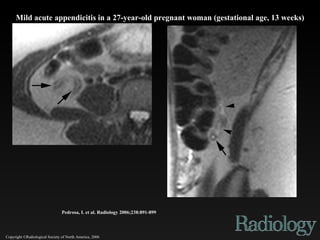

Copyright ©Radiological Society of North America, 2006 Pedrosa, I. et al. Radiology 2006;238:891-899 Mild acute appendicitis in a 27-year-old pregnant woman (gestational age, 13 weeks)

Copyright ©Radiological Societyof North America, 2006 Pedrosa, I. et al. Radiology 2006;238:891-899 Mild acute appendicitis in a 27-year-old pregnant woman (gestational age, 13 weeks)